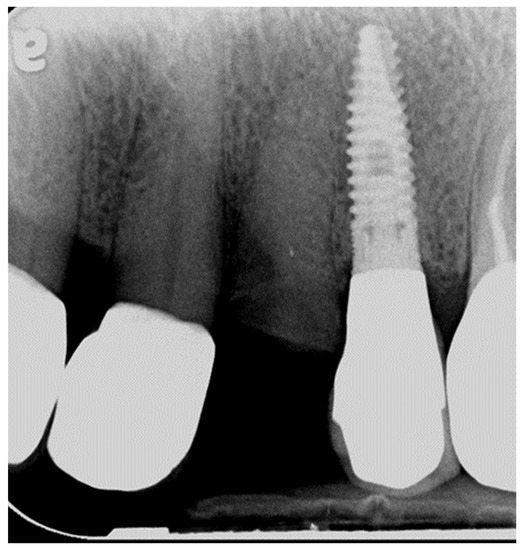

2.5. Clinical and Radiographic Assessments and Classification of Observed Events at the Recall Appointment

3.1. Biological Findings and Implant Survival Rate